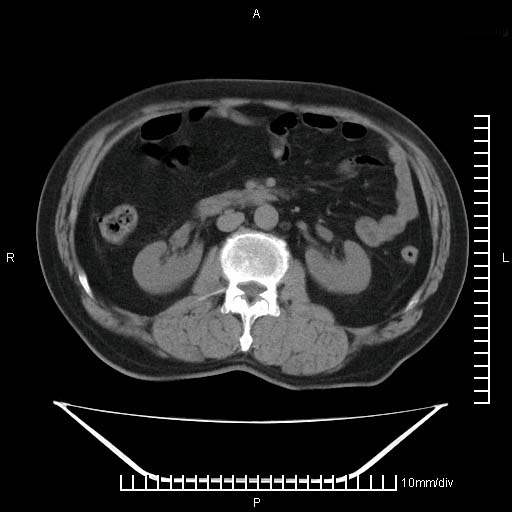

标题: CT25082:肝脏增强:男性,70岁 [打印本页]

标题: CT25082:肝脏增强:男性,70岁

患者以心脏疾病收住院,腹部无明显症状,b超查肝脏有占位。

增强效果不理想。考虑转移,胆囊壁明显增厚,不排除胆囊癌肝转移。

牛眼征,中心坏死无强化,外缘强化,最外缘又见低密度,考虑转移,与脓肿鉴别

肝内多发转移瘤,右下肺炎症并少量胸水。胃壁增厚建议胃镜,胰尾部“病变”为肠管。

1)肝脏多发性转移瘤(不排除胰尾癌转移所致可能)。2)腹水。3)右侧少量胸腔积液。

ct25082 结果:转移瘤

外院mr结果:胰尾恶性占位。